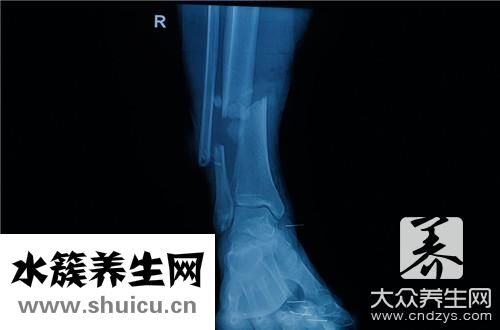

2、踝關節干骨不連

踝關節干骨不連指踝關節干骨骨折處軟組織遮蓋少,造成 滋潤主動脈及營養成分血管易受損害,下骨折段供血不夠,易產生骨折不愈合。